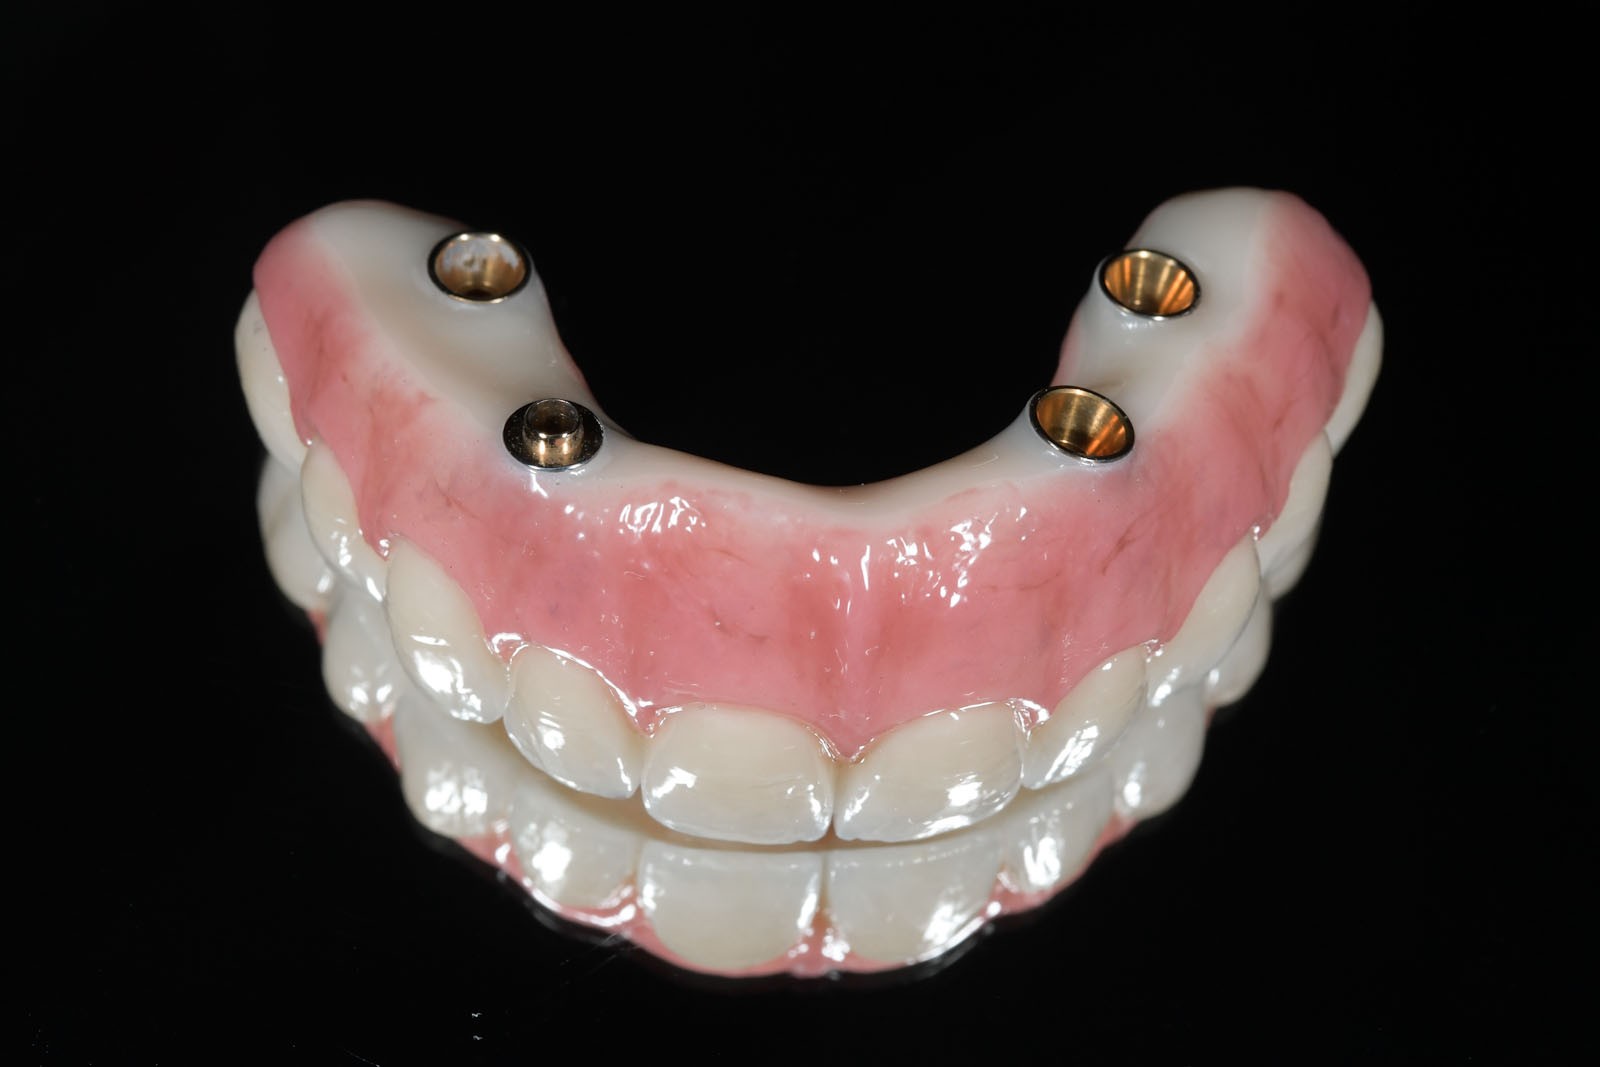

Do uzupełnień protetycznych ruchomych zalicza się protezy, które pacjent w dowolnym momencie może wyjmować z ust. Są to całkowite lub częściowe ruchome protezy akrylowe, nylonowe lub acetalowe oraz wykonane na bazie konstrukcji metalowej protezy szkieletowe. Wymienić tu należy również ruchome protezy typu overdenture wsparte na implantach.

Ciągle powszechnie stosowanym uzupełnieniem protetycznym jest całkowita proteza osiadająca. Zaletami tego rozwiązania są ogólna dostępność, prostota i krótki czas wykonania. Często o wyborze protezy całkowitej decyduje niski jej koszt oraz zadowalający efekt estetyczny w krótkim czasie. Wadę stanowi mały komfort użytkowania oraz stale zanikające podłoże kostne pod protezą, powodowane uciskiem. Proteza tylko w niewielkim stopniu odtwarza utraconą funkcję żucia, a ze względu na pokrycie podniebienia przez płytę protezy, upośledzone zostaje odczuwanie smaku i temperatury spożywanych potraw. W zależności od stanu kości szczęk i żuchwy rozwiązaniem alternatywnym dla pacjenta są uzupełnienia protetyczne wsparte na implantach.

W związku z ich użytkowaniem skala komfortu dla pacjenta zależy od tego, czy są to ruchome protezy Overdenture oparte jedynie na implantach, które poprawiają stabilizację protez zębowych, czy też na stałe mocowane na wszczepach mosty. W ślad za wyborem rodzaju mocowania protez idzie jakość odbudowy protetycznej. Protezy Overdenture są wykonane z materiału kompozytowego lub akrylu, natomiast mosty są wykonane z ceramiki.